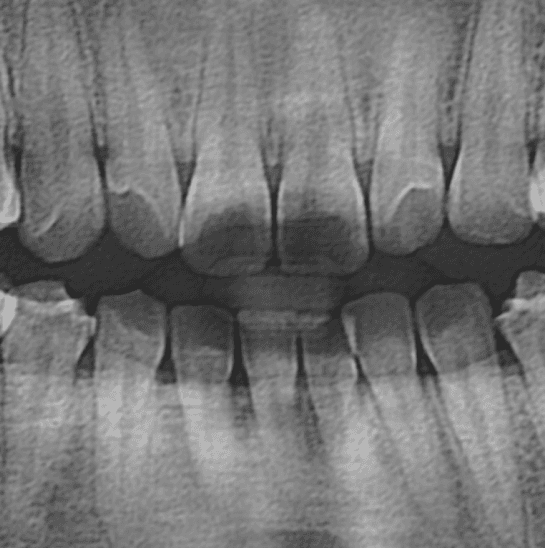

Panorama X-ray

판독 보조

X-ray로 찍은 파노라마 영상을 병원 서버에 자동으로 업로드하여, 치과 우식증(Caries), 치근단치주염(Apical periodontitis) 의심 부위와 치조골 레벨,신경 치료, 임플란트, 보철물 등을 실시간으로 표기할수있는 파노를 소개합니다.